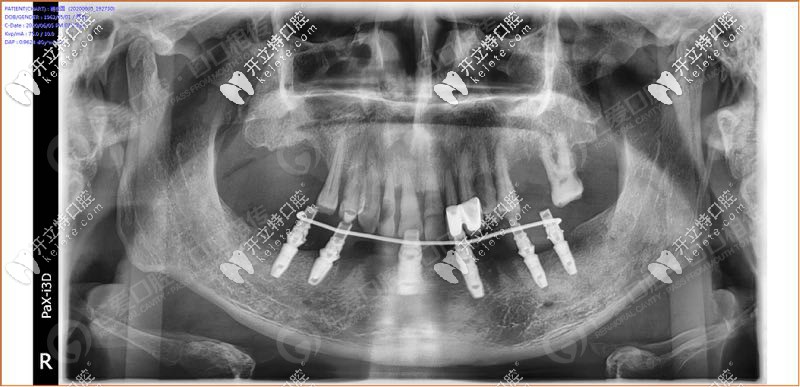

經(jīng)過我院種植醫(yī)生面診,拍片檢查發(fā)現(xiàn),31、32 、33、 34顆牙松動(3度),43顆牙也松動了, 44、45多年前做了烤瓷牙修復(fù),其余牙缺失。

具體設(shè)計(jì)方案:拔除下半口松動牙后,在33、34、36、43、44、46牙窩采用種植導(dǎo)板植入性價(jià)比高的登騰種植體,當(dāng)天帶上牙冠,實(shí)現(xiàn)“當(dāng)天種牙,當(dāng)天用”。

手術(shù)時(shí),我院采用的種植導(dǎo)板技術(shù),術(shù)前設(shè)計(jì),種植體植入方向、位置、角度、深度等一目了然,導(dǎo)板輔助將種植植入到理想位置,有效避開神經(jīng)、血管等危險(xiǎn)區(qū)域,同時(shí)也大大縮短手術(shù)時(shí)間,在拔牙窩即拔即種,沒有切口或切小口,愈合快。

順利植入6顆種植體后,把過渡性臨時(shí)假牙固定到下頜的種植體上實(shí)現(xiàn)了當(dāng)天種牙,當(dāng)天用的即刻負(fù)重種植牙。